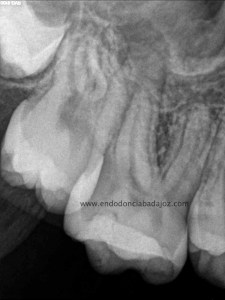

Esta última foto corresponde con un caso de un primer molar superior que la Rx no me esperaba que tuvieses tres conductos mesiales:

Son casos complicados, este en particular, por la ligera curva apical, que se agrava con la curva coronal, con lo que debemos aliviar modificando la apertura y acceso del tercio coronal con ultrasonidos e instrumentación.